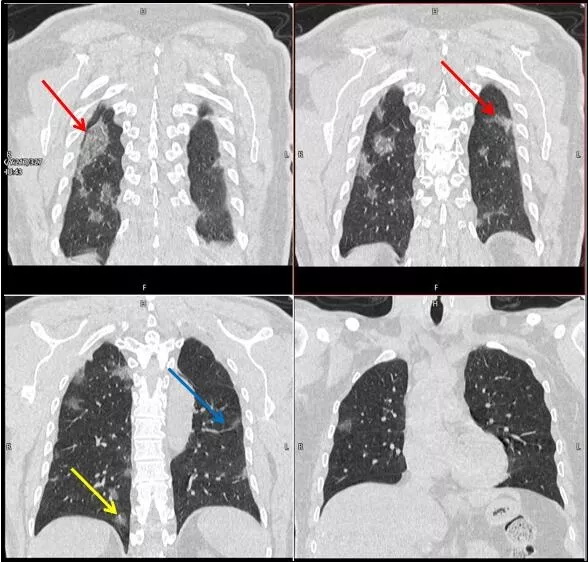

武漢大學(xué)中南醫(yī)院影像科副主任張笑春教授發(fā)現(xiàn),目前武漢市家庭聚集性發(fā)病較多,而且大多起病隱匿,一次甚至多次核酸陰性,無(wú)任何臨床癥狀,CT檢查卻已顯示為病毒性肺炎特征。

為了盡快篩查新型冠狀病毒肺炎患者,醫(yī)院會(huì)選擇影像診斷作為早期發(fā)現(xiàn)新型冠狀病毒感染的肺炎的重要一環(huán)。

CT為當(dāng)前首選篩查與診斷的主要影像學(xué)手段,胸部CT的病毒性肺炎檢出率高。

方舟CT(CT Ark)可以滿足全面的臨床功能,配置16層、32層、64層、128層CT,實(shí)現(xiàn)了低劑量掃描要求,配合NDI微劑量迭代技術(shù),智能毫安調(diào)控技術(shù),使各種場(chǎng)合下、各部位低劑量掃描得以實(shí)現(xiàn);超高分辨率CT病灶靶掃描,使病灶的密度顯示更加精確,能夠顯示病灶內(nèi)輕度的密度變化,有利于小病灶的密度定量分析和及時(shí)診斷。